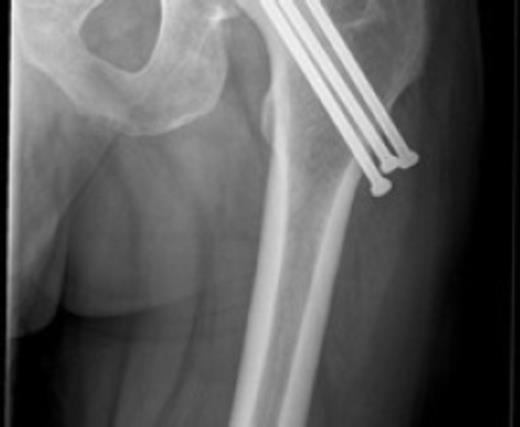

Posterior dislocation of the femoral head with no associated acetabular fracture

Antero-posterior radiograph of the pelvis confirmed a displaced transcervical femoral neck fracture with associated dislocation of the femoral head. Computed-tomography, confirmed a posterior dislocation of the femoral head with no associated acetabular fracture (Fig. 1,2,3).